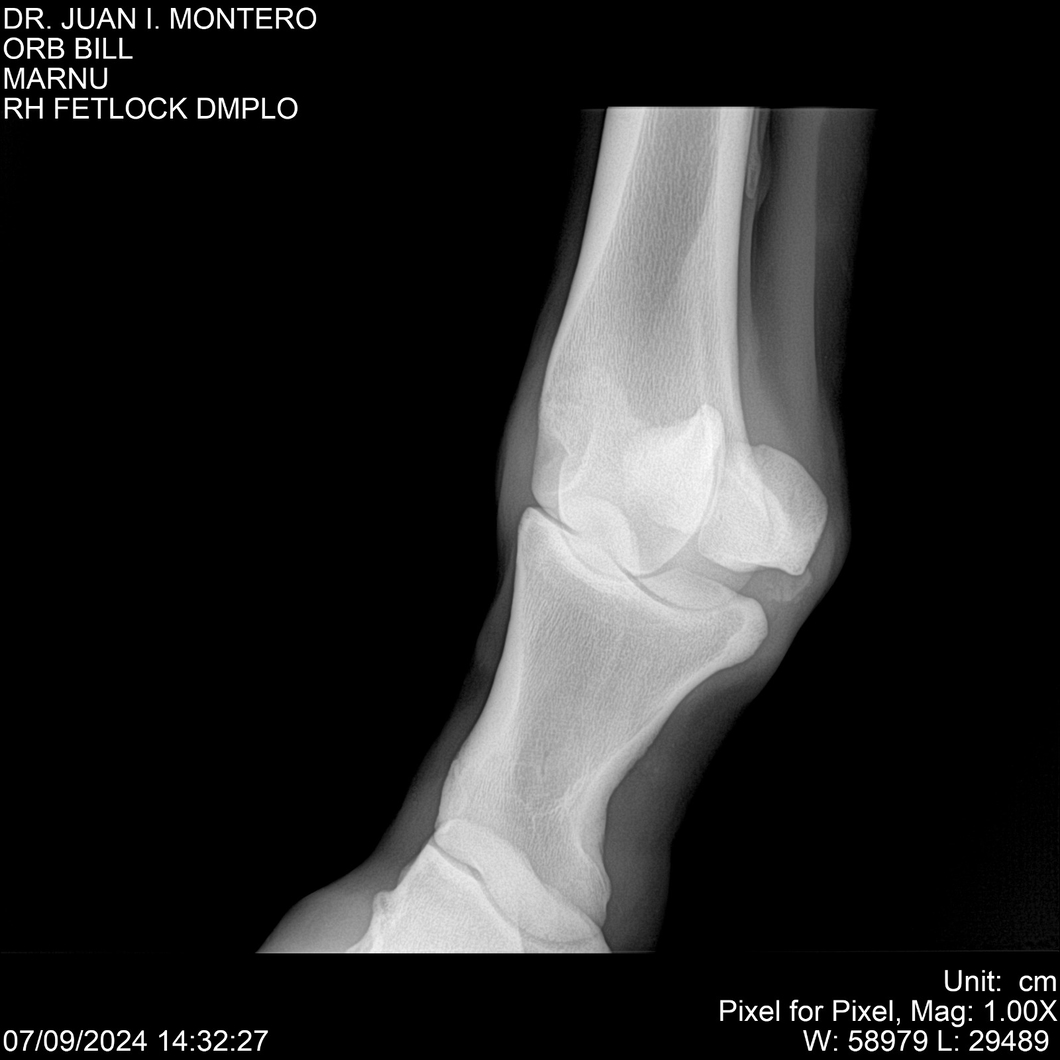

LOTE 7, ORB BILL 🔥 🔥 🔥 Lote Anterior Volver al remate Lote Siguiente Ficha Contacto Montevideo - Ficha del Lote Identificador: #282523 Categoría: Yeguarizos Montevideo - 83 Visualizaciones ClicData Contacto Empresa: Abelenda N. R., Walter Hugo Nombre*: Teléfono* : E-mail* : Mensaje Enviar Registrese gratis Este contenido Exclusivo está disponible sólo para usuarios registrados Ingresar